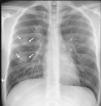

Varón de 24 años con fiebre e infiltrados pulmonares

A 24-year old man with fever and pulmonary infiltrates